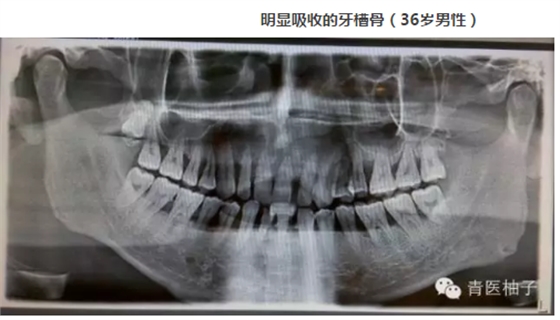

牙周病是指發(fā)生在牙支持組織(牙周組織)的疾病,包括僅累及牙齦組織的牙齦病和波及深層牙周組織(牙周膜、牙槽骨、牙骨質(zhì))的牙周炎兩大類。牙周疾病是常見的口腔疾病,是引起成年人牙齒喪失的主要原因之一,也是危害人類牙齒和全身健康的主要口腔疾病。